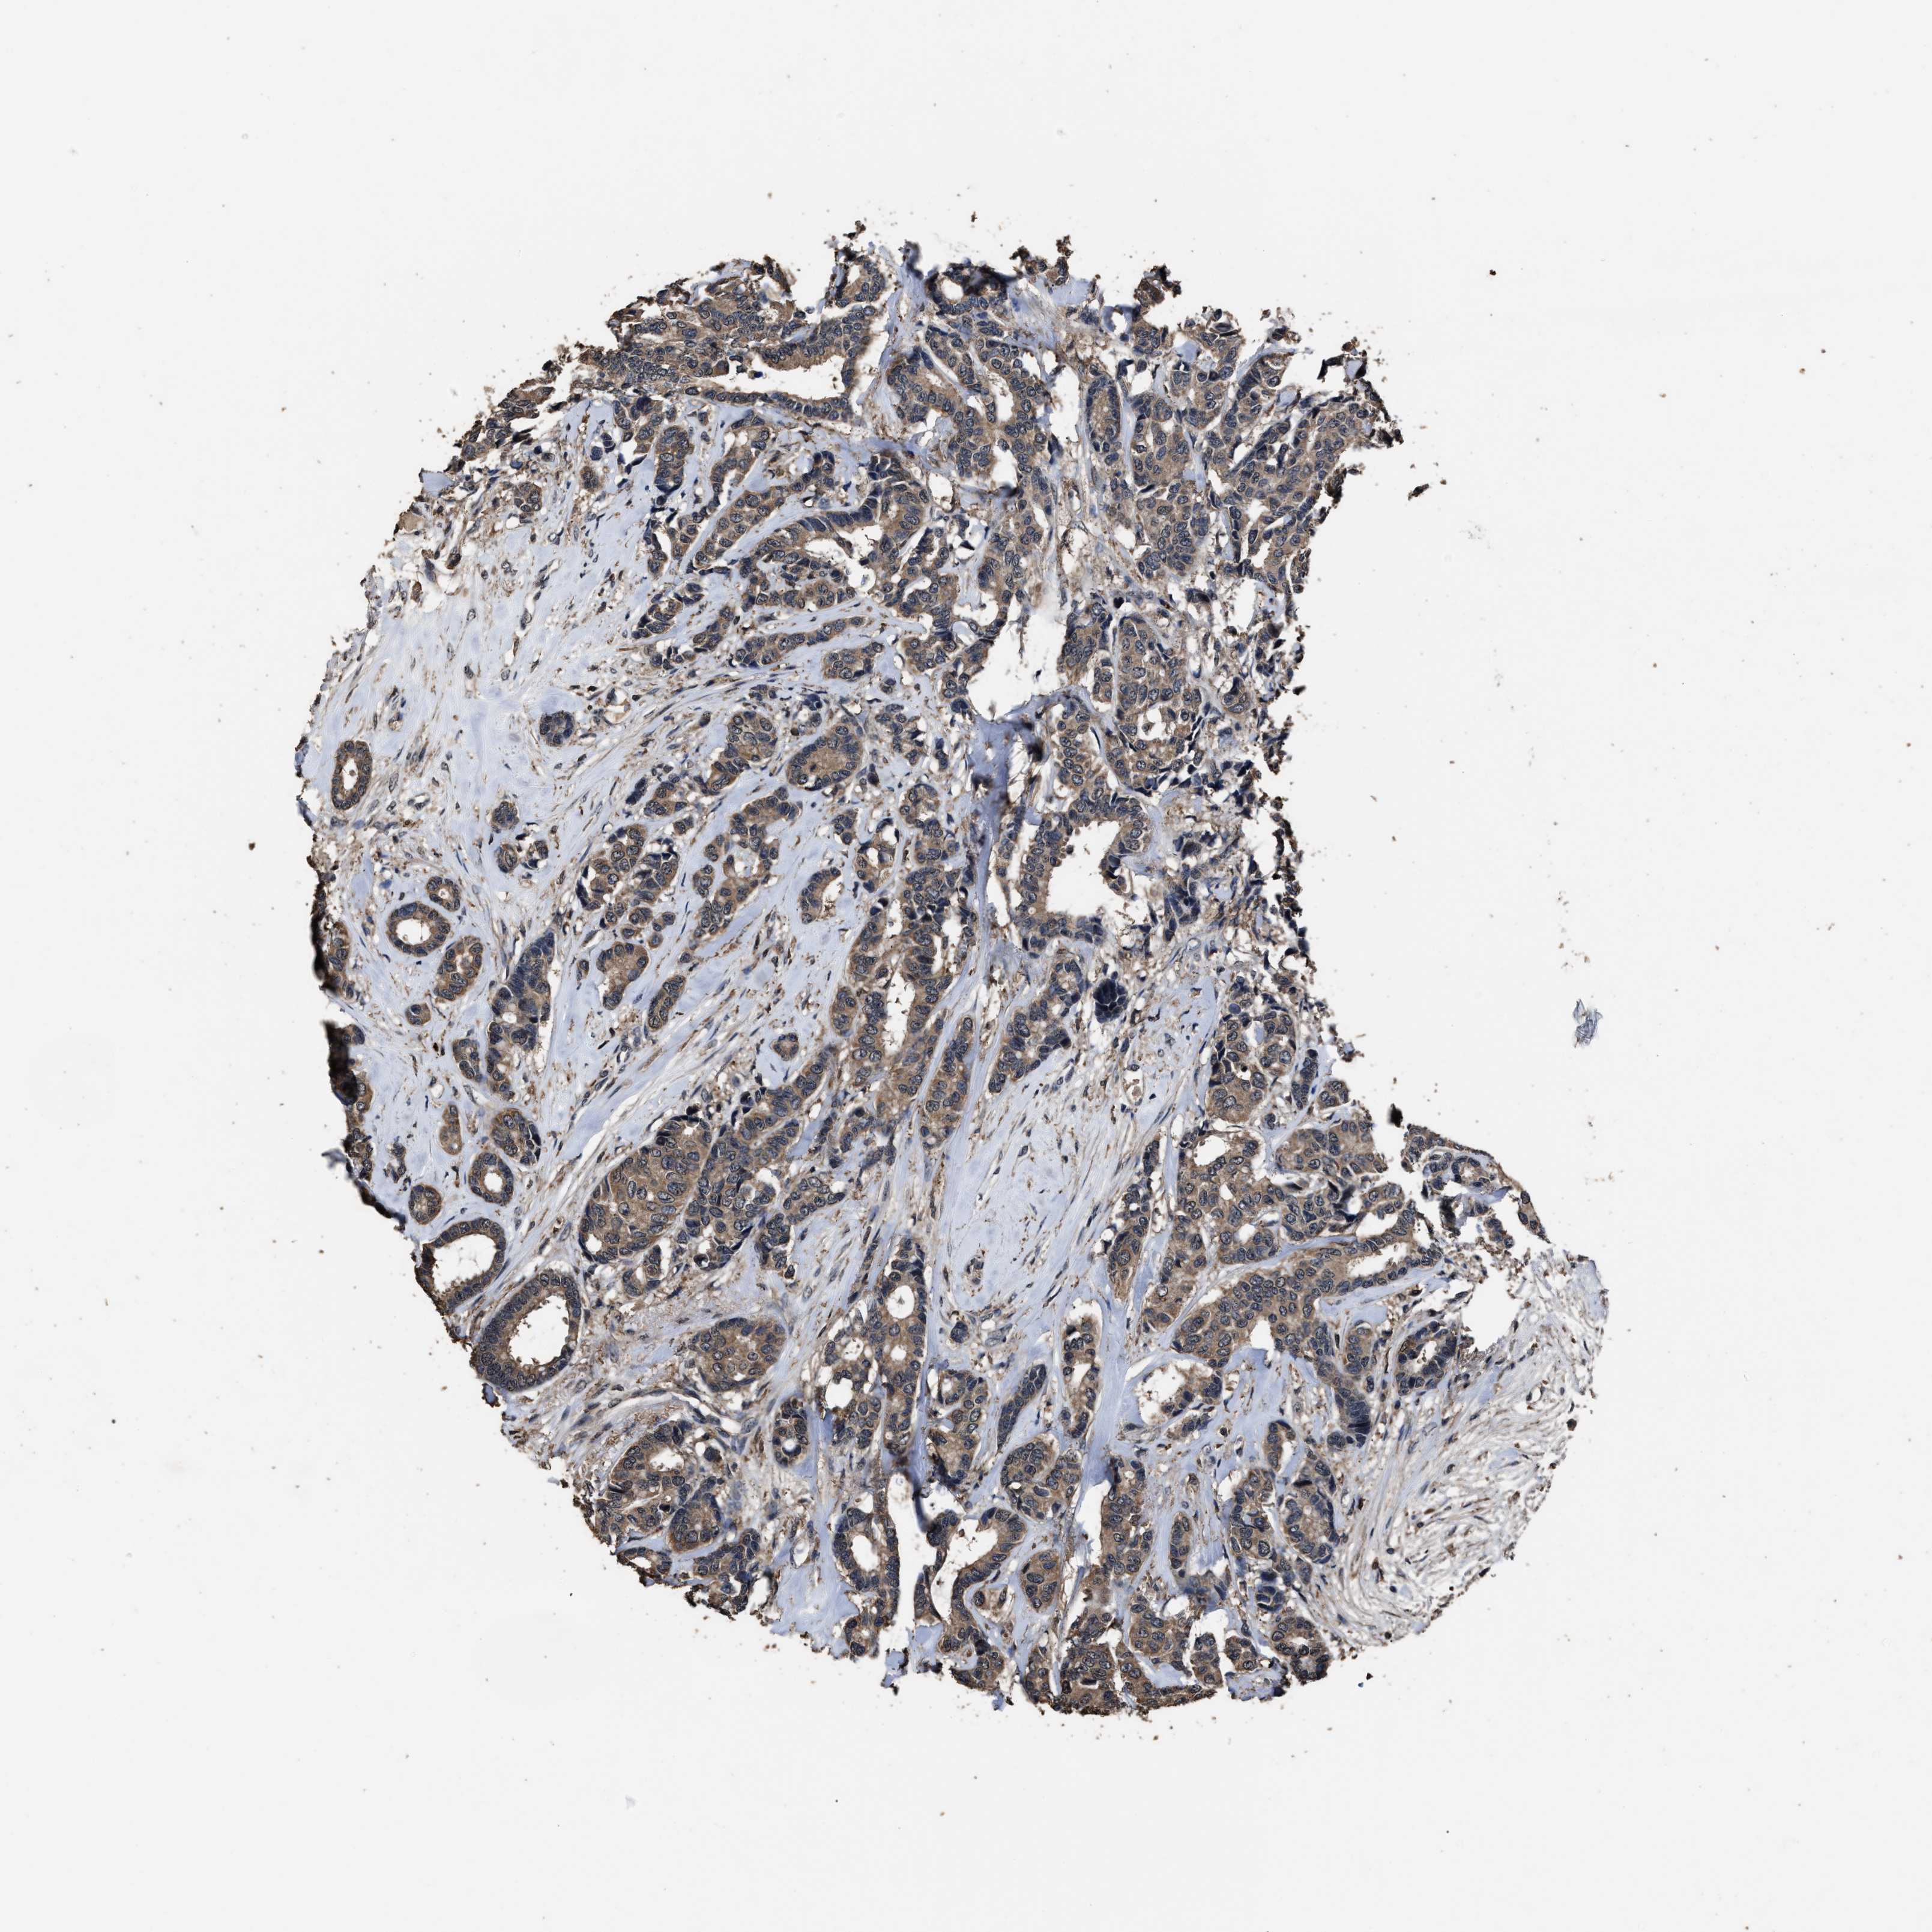

CANCER BREAST CANCER Show tissue menu

BRCA TCGA BRCA VALIDATION PROTEIN EXPRESSION

Breast cancer

Human cancer

RSBN1L is not prognostic in Breast Invasive Carcinoma (TCGA)